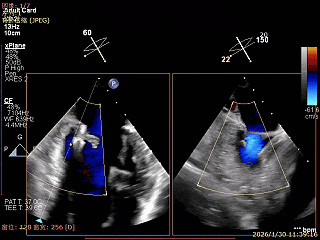

Bicomm切面看2区脱垂

上Color,可见反流主要来自于3区

X-Plane切面切1区未见明显异常

1区上Color,未见反流来源

X-Plane切面切2区可见前叶Flail

2区上Color,可见反流来源

X-Plane切面切3区可见前叶脱垂

3区上Color,可见反流来源